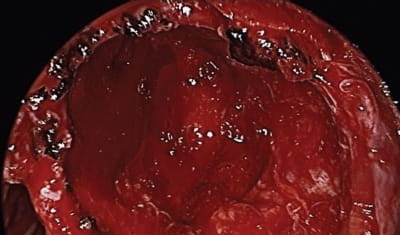

Post resection view. Post resection view. The posterior wall of the maxillary sinus has been widely opened. Posterioinferiorly are the pterygoid plates and superiorly the lesion was in close approximation to the temporal lobe. Within the anterior superior region of the resection cavity the orbit is dehiscent. The internal maxillary artery was identified and preserved inferiorly.